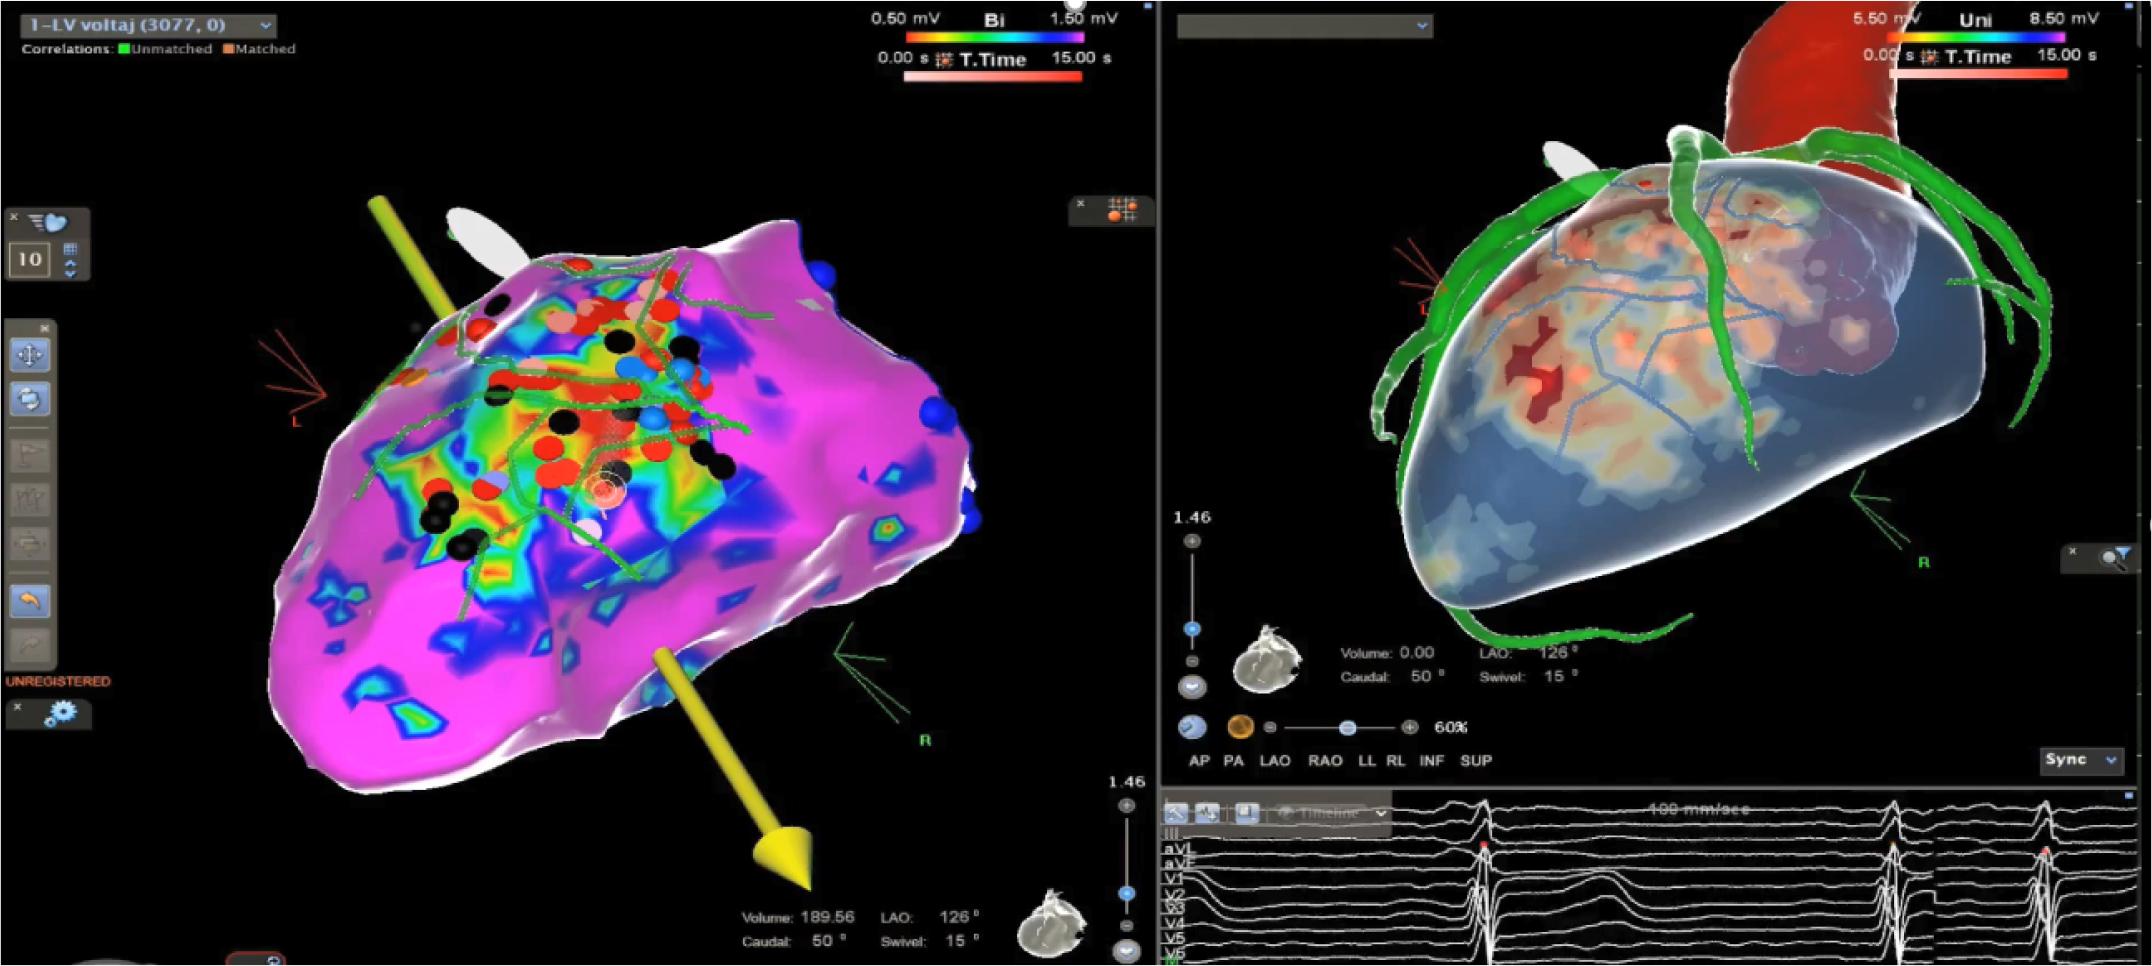

Mapping was conducted with Carto 3 Biosense Webster and Stereotaxis Remote Magnetic Navigation System. A detailed electro-anatomical map of more than 3000 points obtained during sinus rhythm was fused with LGE-CMR/MDCT data, using coronary artery ostia as a reference point. The majority of the conduction channels were anatomically consistent between the EAM and LGE-CMR/ MDCT fusion map. (Fig. 4)

Multimodal image integration. Right: Fusion between MDCT and LGE-CMR PSI Map (ADAS 3D Software). Left: Integration with EAM (Biosense – Webster Carto 3 Navigation System)